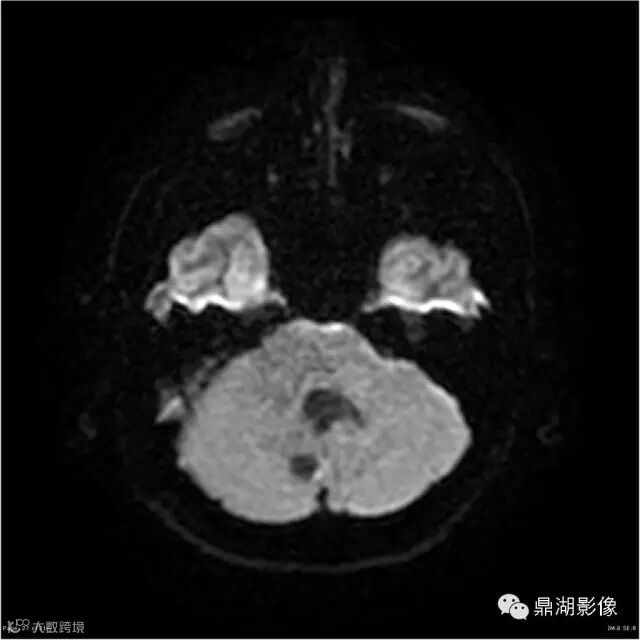

Axial DWI

本例为一例实质性血管母细胞瘤。实性血管母细胞瘤CT平扫示病灶呈等或高密度,增强后可见明显强化。MRI平扫通常病灶很不均质,T1呈稍低信号为主的较混杂信号,T2呈等、高信号,DWI通常呈低信号或等信号。文献报道,实性血管母细胞瘤较典型的表现为瘤内及瘤周扩张的流空血管影,瘤周中、重度水肿。因此,小脑半球区的单发肿块伴流空血管影,周围大片水肿以及增强后肿块明显强化"形态规则"边界清楚,此时应将实性血管母细胞瘤考虑在内。

实性血管母细胞瘤须与脑膜瘤、淋巴瘤、室管膜瘤等鉴别;脑膜瘤,为脑外肿瘤,极少发生囊变,多数可见“脑膜尾征”,出血及坏死少见,瘤周水肿较轻;淋巴瘤,常位于深部脑组织,无血管流空影,DWI上呈高信号,文献报道,实性血管母细胞瘤 DWI( b=1000) 呈低信号有助于两者鉴别;室管膜瘤一般瘤周无蚓状流空的肿瘤供血动脉,增强时强化程度不及血管母细胞瘤。